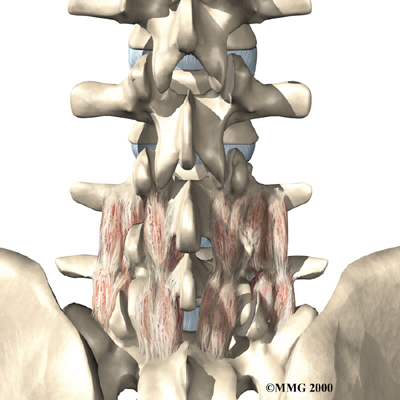

The next part of our program will include a series of strengthening exercises for the abdominal and low back muscles. Working these core muscles helps our patients begin moving easier and lessens the chances of future pain and problems. Aerobic exercises such as walking or swimming are used for easing pain and improving endurance.

A primary purpose of your physical therapy is to help you learn how to take care of your symptoms yourself and prevent future problems. We'll provide you with a home program of exercises to continue improving flexibility, posture, endurance, and low back and abdominal strength. Our physical therapist will also discuss strategies you can use if your symptoms flare up.